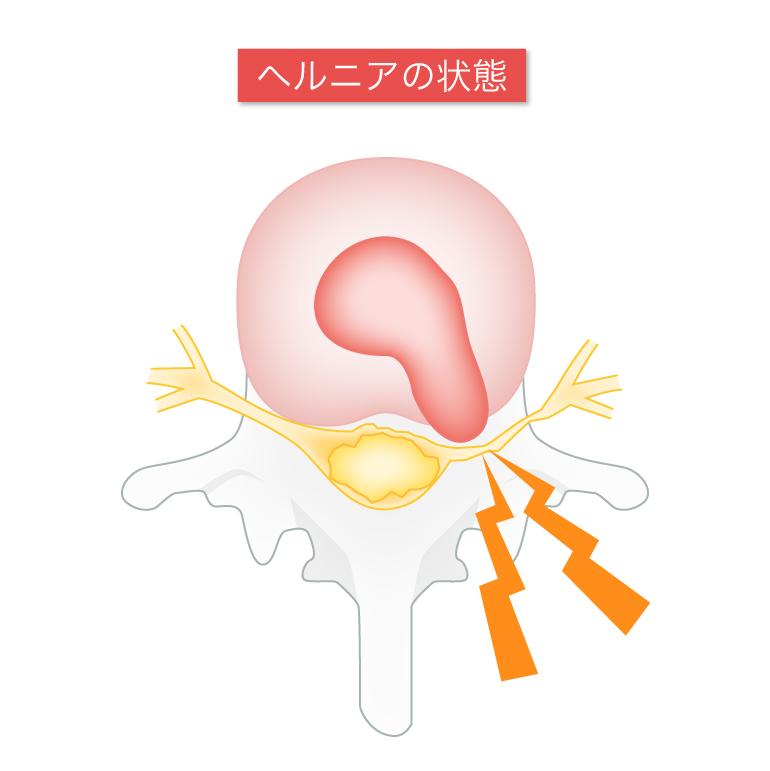

腰椎椎間板ヘルニアはどんな病気ですか?

椎間板内の組織の一部が飛び出して神経を圧迫する病気です。

「腰椎椎間板ヘルニア」は、腰の痛みや足の痛み、しびれといった症状が出ます。症状が腰の痛みだけしか出ないこともあります(10%程度)。

重症化すると、足のまひや排尿・排便の障害を生じることがあります。

腰椎椎間板ヘルニアの主な原因は、椎間板にかかる強い圧力です。主には前屈みの姿勢で、急に重いものを持ったり、中腰や下を向く作業が多いと椎間板ヘルニアになりやすいと言われています。

弾力性のある椎間板を持つ若年層は、中腰で重いものを持ったときなど突発的に椎間板が飛び出してしまうことがあり、その場合激痛が走ります。